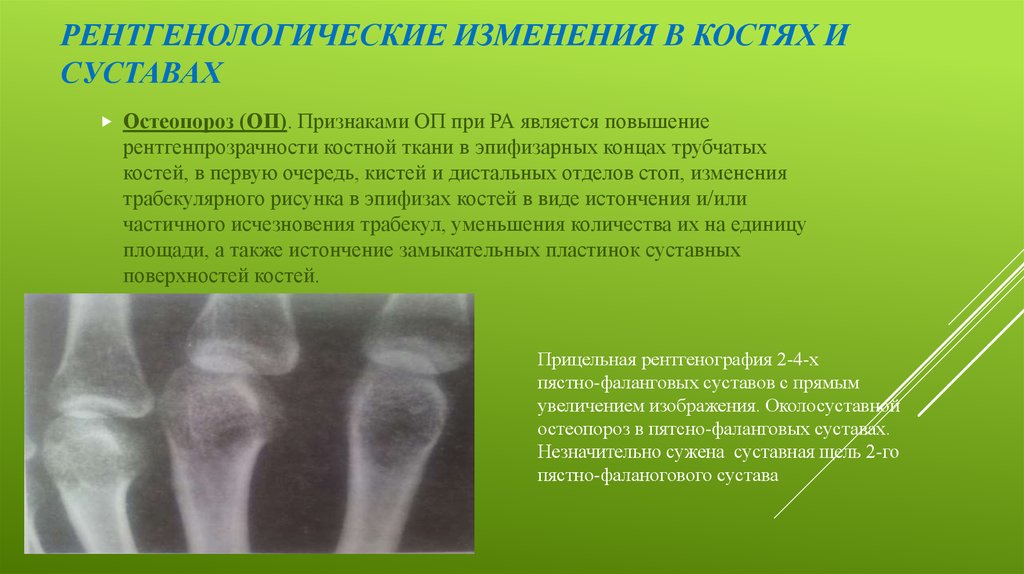

Ревматоидный артрит стопы: рентгеновские снимки и стадии заболевания

Раздел: Визуальный дайджест